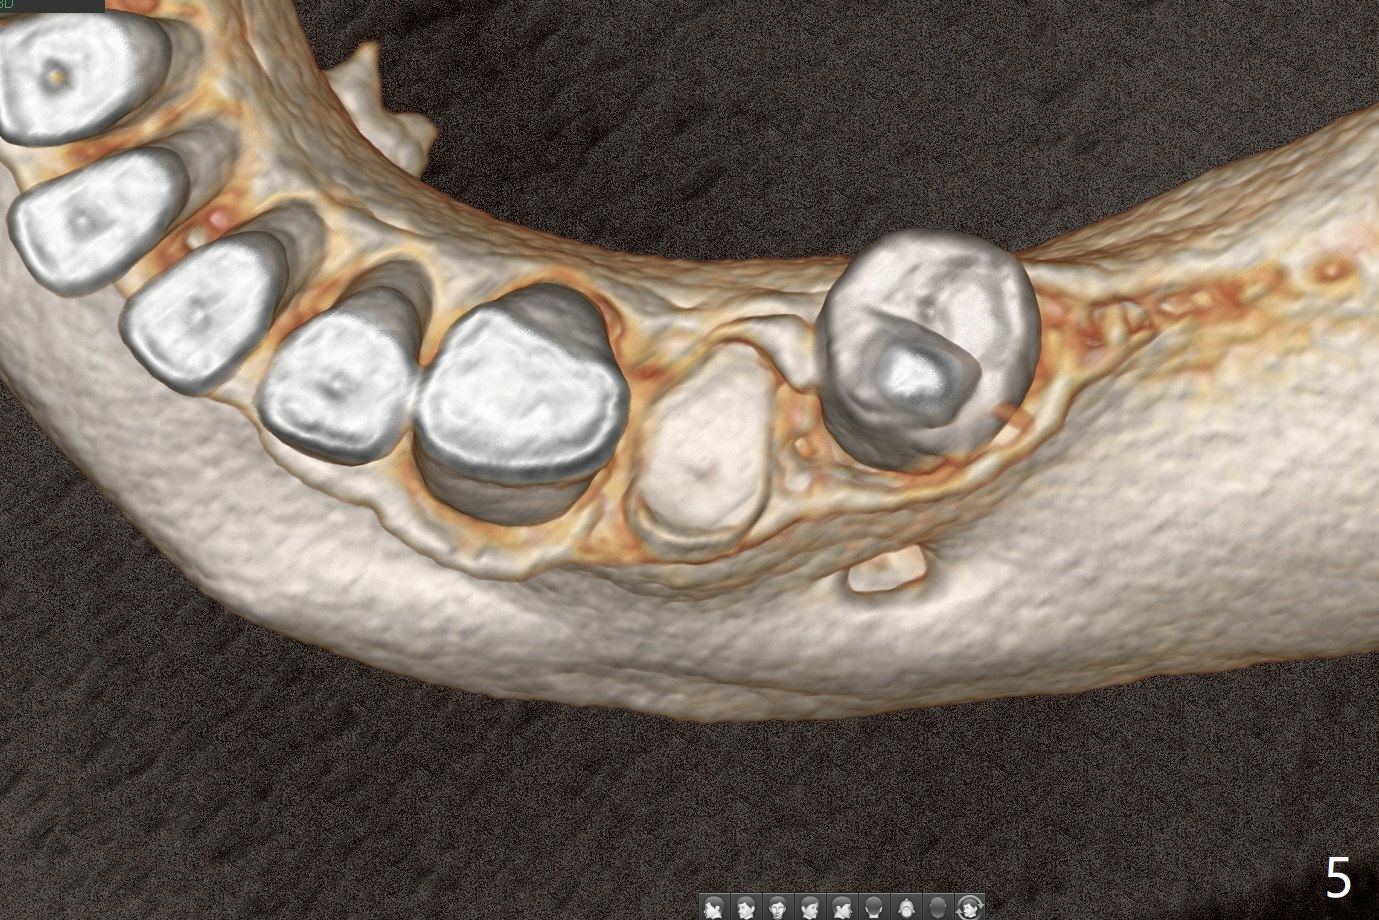

A 52-year-old man chooses to take care of the teeth #21 and 29 first due to finance (Fig.1). The implant diameter should not be too large because of the moderate mesiodistal space (Fig.2,3). Since the buccal plate of #21 is indistinct (socket shield will be done), the implant should be a little more lingually placed than the design in Fig.3, although the implant placement level seems to be acceptable. Socket shield seems to be necessary.